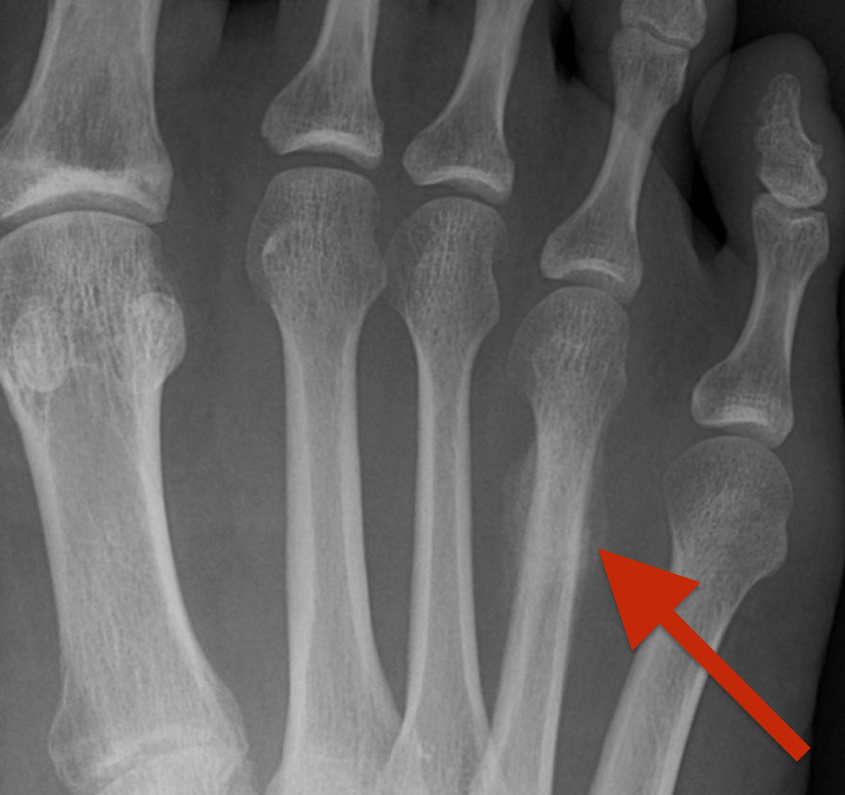

Stress fractures differ from regular fractures in a very distinct way. Regular fractures of bone in the foot result from traumatic injuries like twisting injuries, heavy weight on the foot, or smashing the foot against a harder object, resulting in force that is strong enough to break bones. Stress fractures are caused by much more subtle force that occurs over a long period of time. Repetitive stressful pressure from activity in some instances can cause microscopic damage in the inner content of the bone. As these stress forces continue to act on the bone, the damage advances. Eventually, an interior fracture occurs in the bone, causing pain, swelling, and warmth. In some instances the stress fracture can eventually lead to a regular fracture as the shell of the bone fractures with the interior.

What is the difference between a stress fracture in the foot, and a regular fracture?